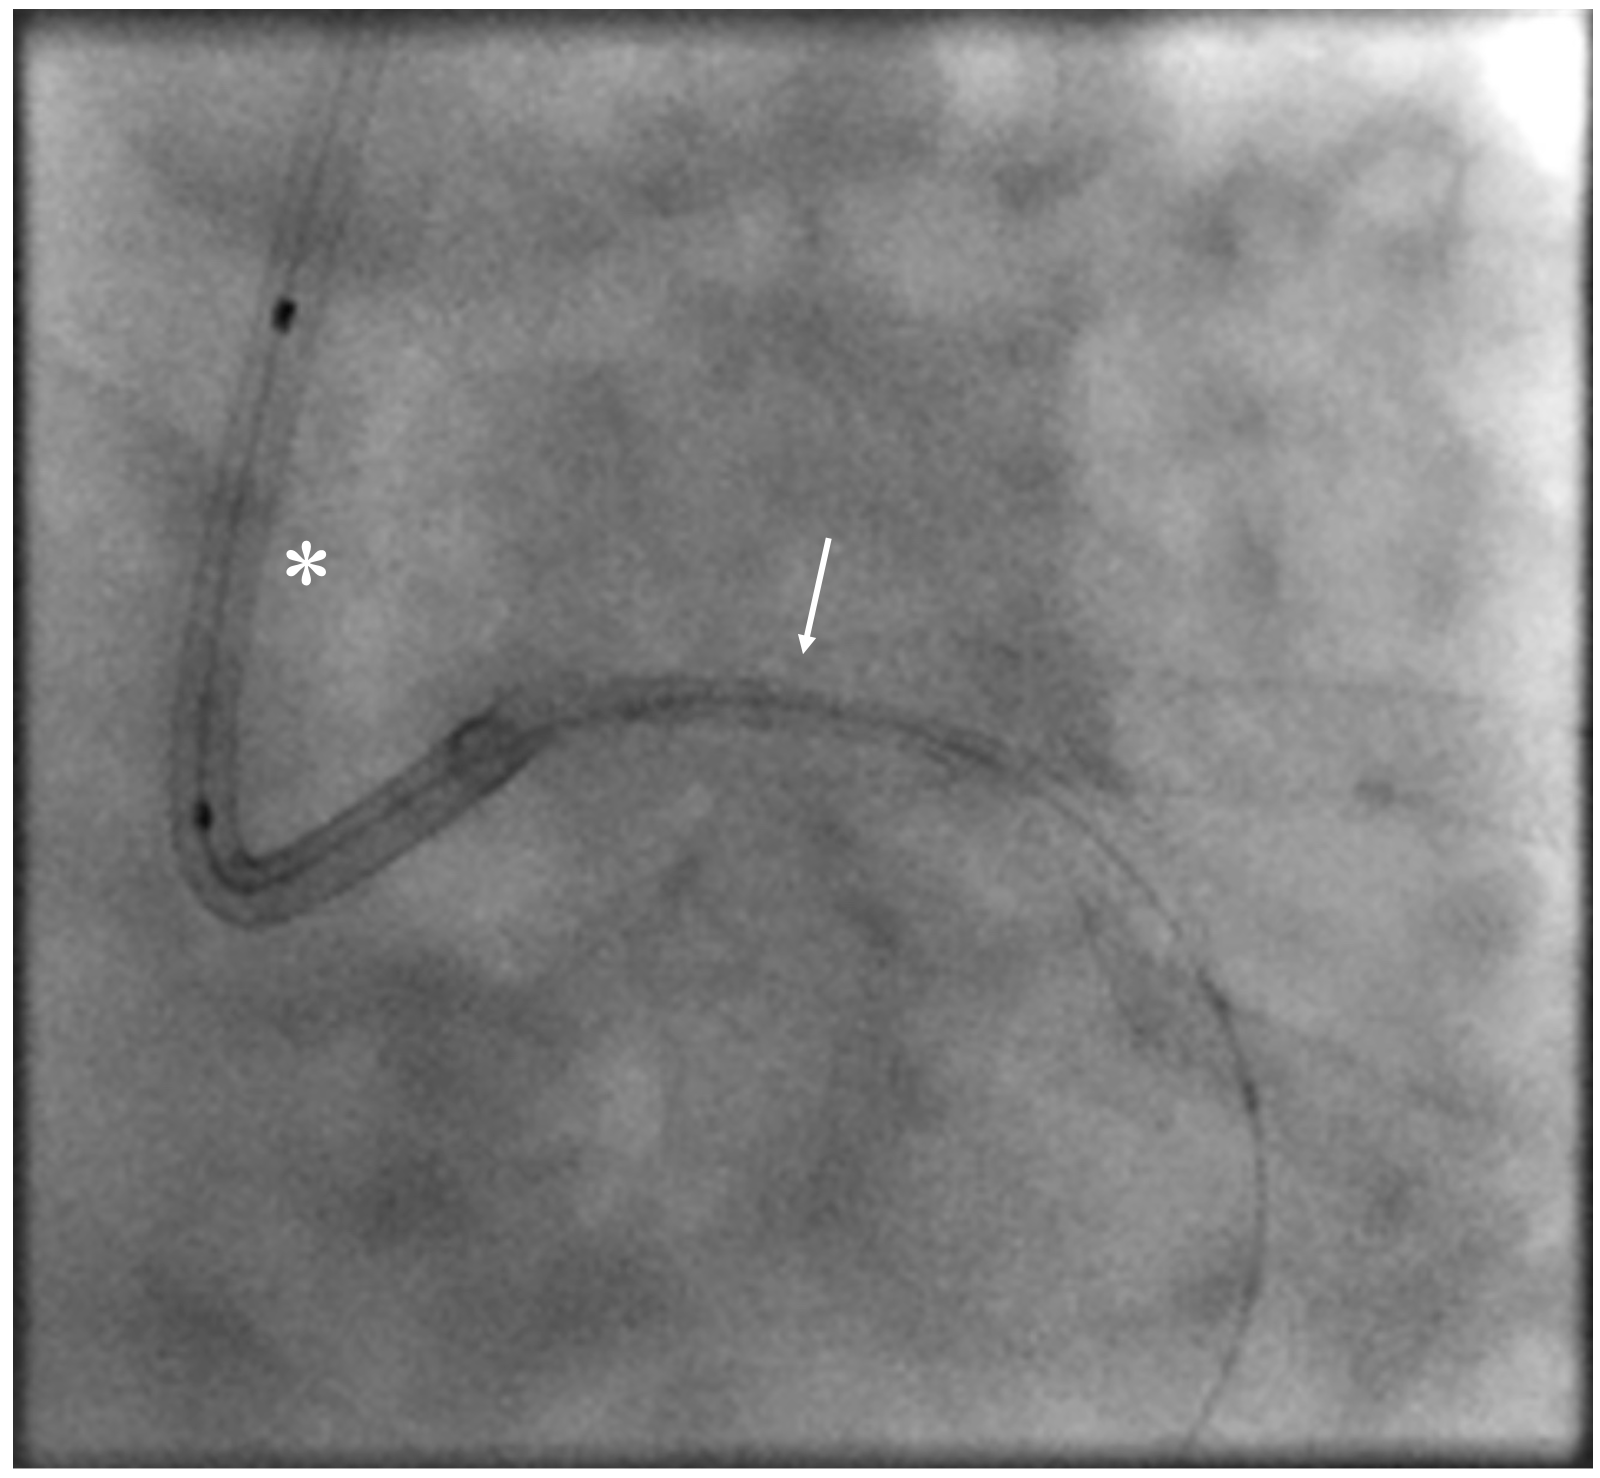

A 71-year-old man who had undergone percutaneous transluminal coronary angioplasty (PTCA) in 2013 was admitted for unstable angina. Coronary angiogram showed 2 de novo lesions at the proximal and distal left circumflex artery (LCX) (Figure 1A). PTCA was performed transradially via a 6-French (Fr) sheath. With a 6-Fr extra-backup 3.5 guide catheter engaging to the left main coronary artery (LM), a 2.5 x 18-mm drug-eluting stent (DES) was delivered to the distal LCX lesion but was inadequate for complete lesion coverage (Figure 1B). During retrieval, the stent was found dislodged at the distal LM bifurcation (Figure 1C).

Distal small balloon retrieval was unsuccessful (Figure 1D). With the help of the Balloon-Assisted Guide-extension (BAG) system, the stent could be optimally positioned at the proximal LCX lesion by forward pushing with a 6-Fr Guideliner V3 catheter (Teleflex) and backward pulling by the small balloon (Figure 1E and F; Video). It was then deployed by sequential balloon dilatation with good expansion (Figure 1G and H). Another 2.5 x 24-mm DES was deployed at the distal LCX, which gave an excellent final angiographic result (Figure 1I and J).